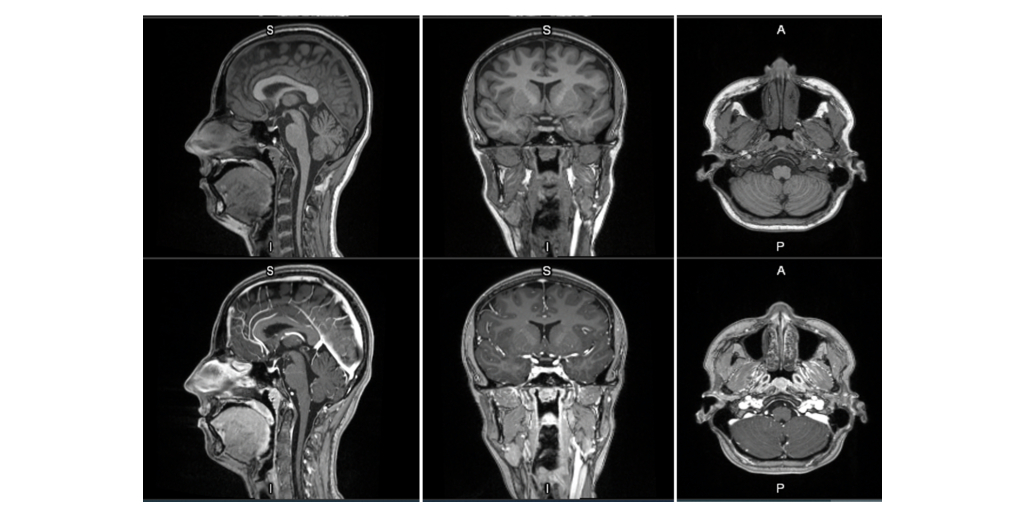

MRI contrast agents enhance the visualization of abnormal structures or lesions during imaging procedures and help clinicians better distinguish between healthy and diseased tissue. Mangaciclanol is intended for general-purpose MR imaging and demonstrates comparable relaxivity (the ability to enhance signal intensity) to market-leading gadolinium-based agent, gadobutrol, with early clinical images suggesting similar diagnostic capability. Unlike gadolinium, which is a rare-earth metal, manganese is present in our food, and is an endogenous element, naturally occurring and autoregulated in the body. The macrocyclic ‘cage-like’ structure of mangaciclanol lessens the possibility of retention.